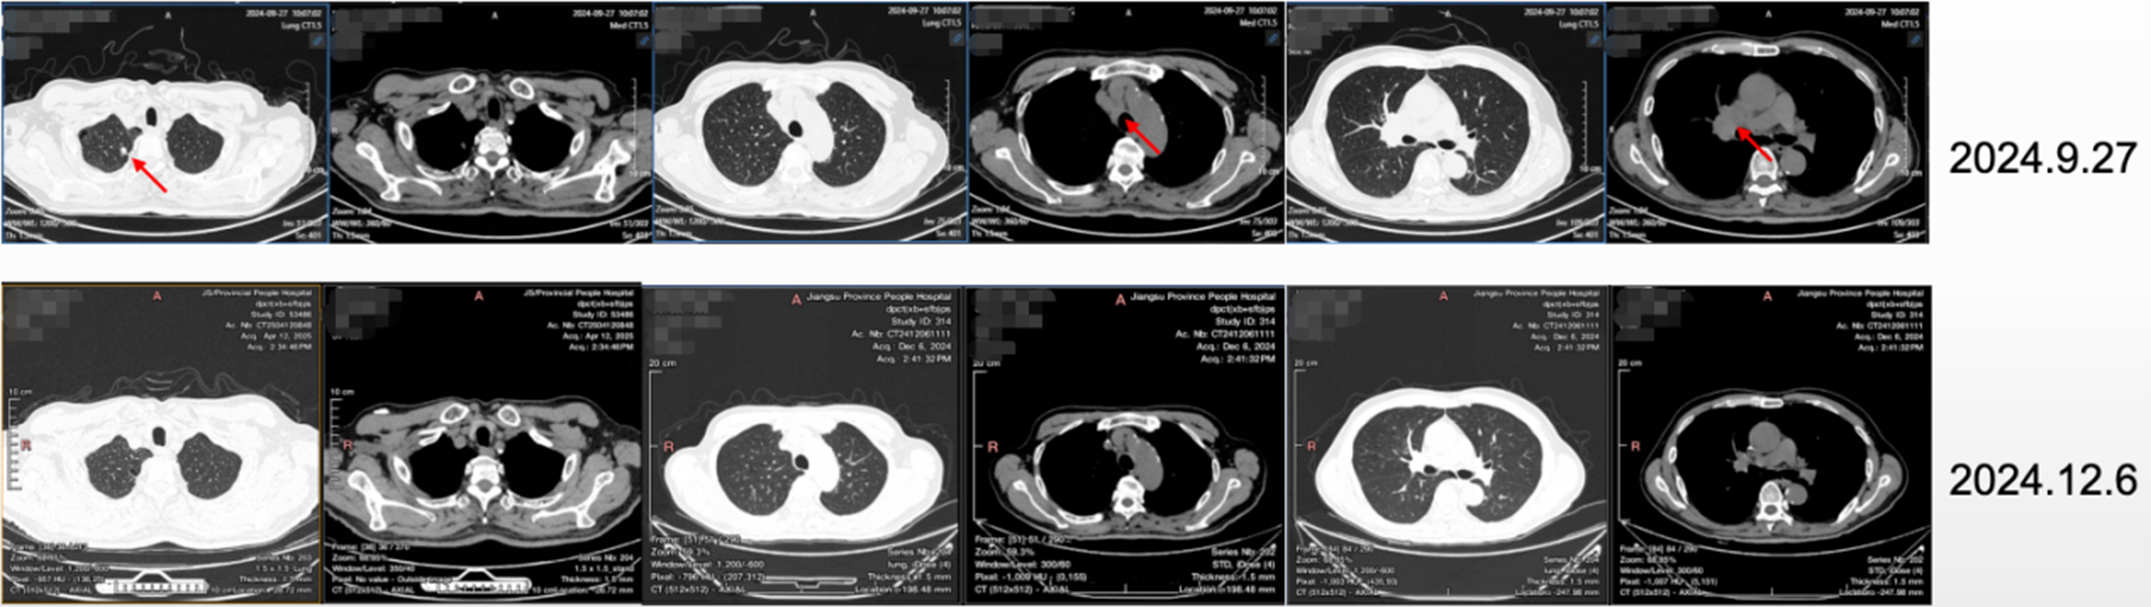

• 治疗2周期后,2024.12.6复查CT,达部分缓解(PR)。

图2 治疗2周期后复查CT结果

• 后持续规律治疗及随访,复查CT结果显示,病灶持续缓解。

图3 治疗11周期后复查CT结果